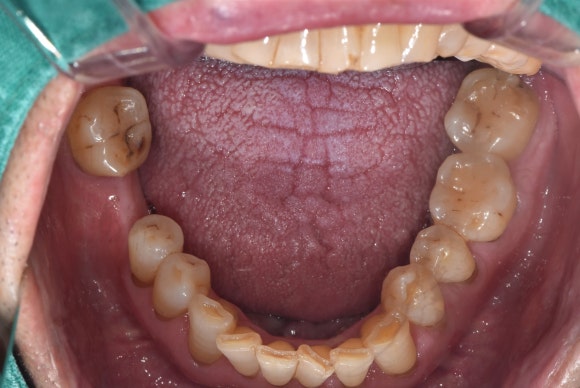

20250404

기둥에 크라운을 붙입니다.

절묘한 각도로, 매우 정밀한 크라운이 만들어졌습니다.